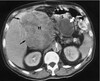

A

Cirrhosis of the Liver ## Footnote -Not filled arrow: Atrophy of liver -White arrow: Collateral blood flow (blood vessels larger and shunted off to a collateral flow-blood becomes more visible) -Surrounding the abdomen: Ascites

241